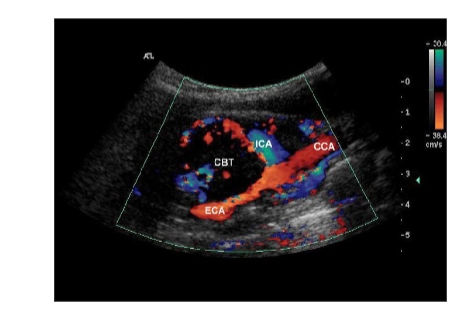

What causes a carotid body tumor (CBT) what is it?

its a tiny structure that controls PH, blood gas and BP, located at the carotid bifurcation

presents with palpable neck mass and headache, if untreated can cause stenosis, occlusion or rupture

On ultrasound it will bow out at the ICA and ECA bifurication